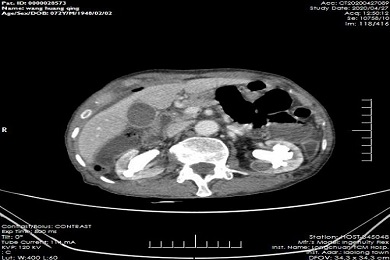

患者以最快的速度完善抽血检查,同时在李嘉医生和值班医生的陪护下行腹部CT以及心电图等术前检查。随后抽血结果数项同时异常超标,呈危急值状态:血浆-D二聚体7550.2ng/L、脑尿钠肽 4531pg/ml、肌红蛋白198ug/L;肾功6项:尿素 18.34mmol/L、肌酐271umol/L、尿酸668umol/L、胱抑素-C 2.93mg/L;血常规:白细胞11.68*109/L、中性粒细胞百分比92.5%、中性粒细胞数目10.80*109/L; C-反应蛋白126.01mg/L;降钙素原17.25ng/ml;CT提示腹腔大量游离气体以及大量腹腔积液,考虑消化道穿孔。